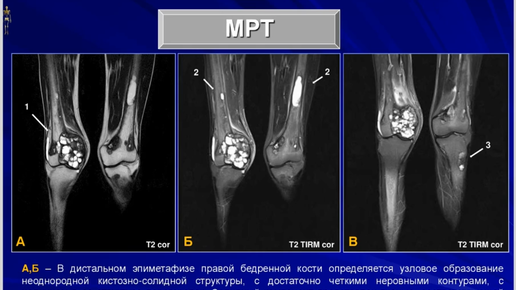

Клиническое наблюдение первичного гиперпаратиреоза